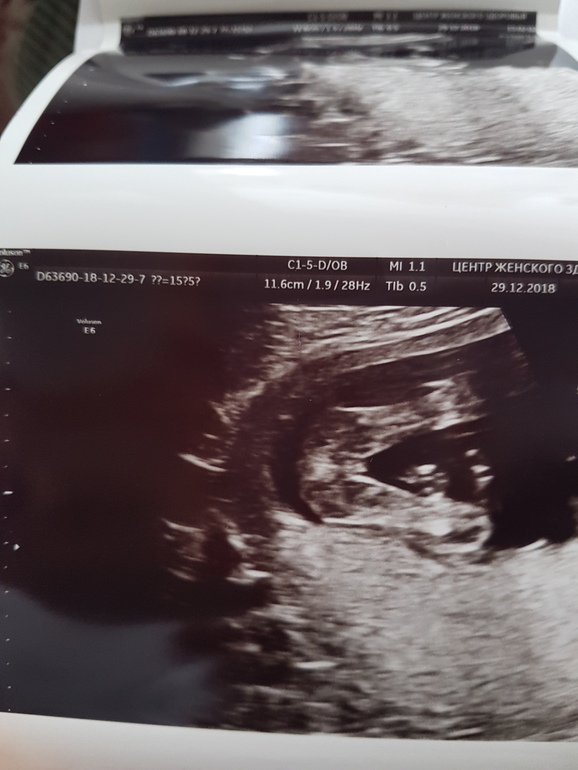

И всё. Хожу, смотрю на фото точно там Она или отрастёт ещё? Покажу два фото, но с одного ракурса. Кто что скажет? Вот честно, я такого ещё ни разу не видела, в 16 недель девочки такие?

Оооо! У нас такой же пирожочек на УЗИ было видно))) Поздравляем с доченькой💐🎉🎈

Ура:)) Вчера показала фото свекрови, она яички там нашла. Села, почитала комментарии опять, отпустило:))

Нету там никаких яичек))) ну предположим это яички. Тогда где сам писюн?😄спрятался)) неееее. Не сомневайся даже. Это точно девочка. У мальчиков по другому там😉

Спасибо тебе, голос разума:)) Я тоже помню Влада в 16 недель, там всё сразу было видно, высматривать не приходилось, а в этот раз слишком мнительная